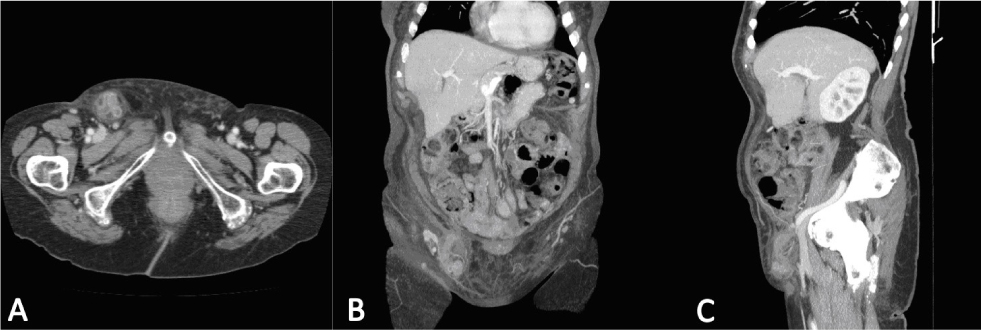

An 86-year-old female came to the emergency department with a 5-day history of a right-sided groin mass which had appeared after an episode of vomiting. The patient reported no change in bowel habits and no further episodes of vomiting. Her medical history included arthrosis treated with anti-inflammatory medication. On physical examination, her vital signs were stable and she was afebrile. The abdomen was soft and non-tender, with a painful right groin mass on palpation (approximately 5x3cm). There was no erythema or crepitus, nor any rebound or rigidity. Laboratory data on admission were as follows: white blood cells 6.28 x103/mm3, with 76.4% neutrophils, and C-reactive protein (CRP) 20.7 mg/L. Abdominal X- ray did not reveal any significant abnormality. A CT was performed and revealed a right femoral hernia with the vermiform appendix in the hernia sac and mural thickening. There were no signs of perforation or abscess (Figure 1).

Contrast-enhanced CT of the abdomen. (A) Axial view: tubular structure containing gas within the femoral hernia. (B) Coronal and (C) sagittal views: tubular structure extending from the caecal base.